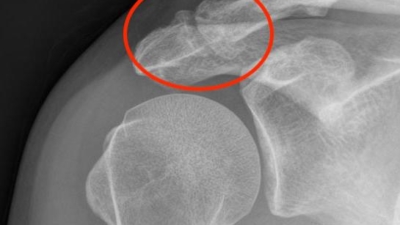

Wanneer een röntgenfoto?

Een röntgenfoto is bij AC gewricht klachten vaak het meest informatieve onderzoek voor de botstructuur.

We zien de gewrichtsspleet (versmald bij artrose), botwoekeringen aan de boven- én onderkant van het gewricht, en eventuele kalkafzettingen.

AC gewricht artrose rontgen

Ook een luxatie of oude fractuur is direct te herkennen.

Waarom de onderkant belangrijk is

Bij AC artrose groeien botwoekeringen vaak naar beneden, richting de ruimte waar de schouderpezen en slijmbeurs doorheen moeten glijden.

Op een röntgenfoto zien we of die botwoekeringen de ruimte voor de schouderpezen (rotator cuff) verkleinen. Dat is op een echo niet te beoordelen.

AC gewricht artrose en pessontsteking

Dit is essentieel voor het behandelplan. Is er alleen artrose boven in het gewricht? Dan volstaat vaak een injectie.

Geven botwoekeringen aan de onderkant ook druk op de pezen? Dan speelt er meer en moet de behandeling daarop worden aangepast.

De beperking van röntgen

Weke delen zijn op een röntgenfoto niet zichtbaar. Het gewrichtskapsel, ontstekingsvocht en de schouderpezen zijn niet te beoordelen. Daarvoor is een echo nodig.

En artrose op een foto betekent niet automatisch klachten. Veel mensen boven de 40 hebben slijtage op de röntgenfoto zonder er ooit last van te hebben.

💡 Bij Orthozorg: Röntgen toont het bot, echo toont de weke delen. Samen geven ze het complete beeld. Daarom combineren we bij AC gewricht klachten vrijwel altijd beide onderzoeken.